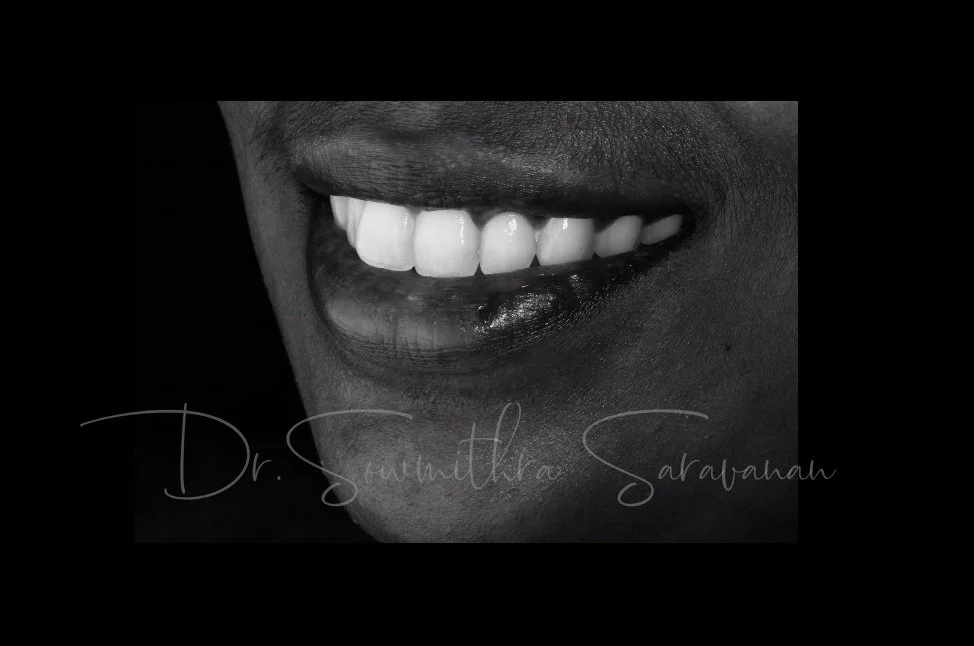

smile makeover

Smile Journey!

May be it is too simple to treat but the way this smile makeover made a difference in her life is immense! thats how wonderful smile curves are created!